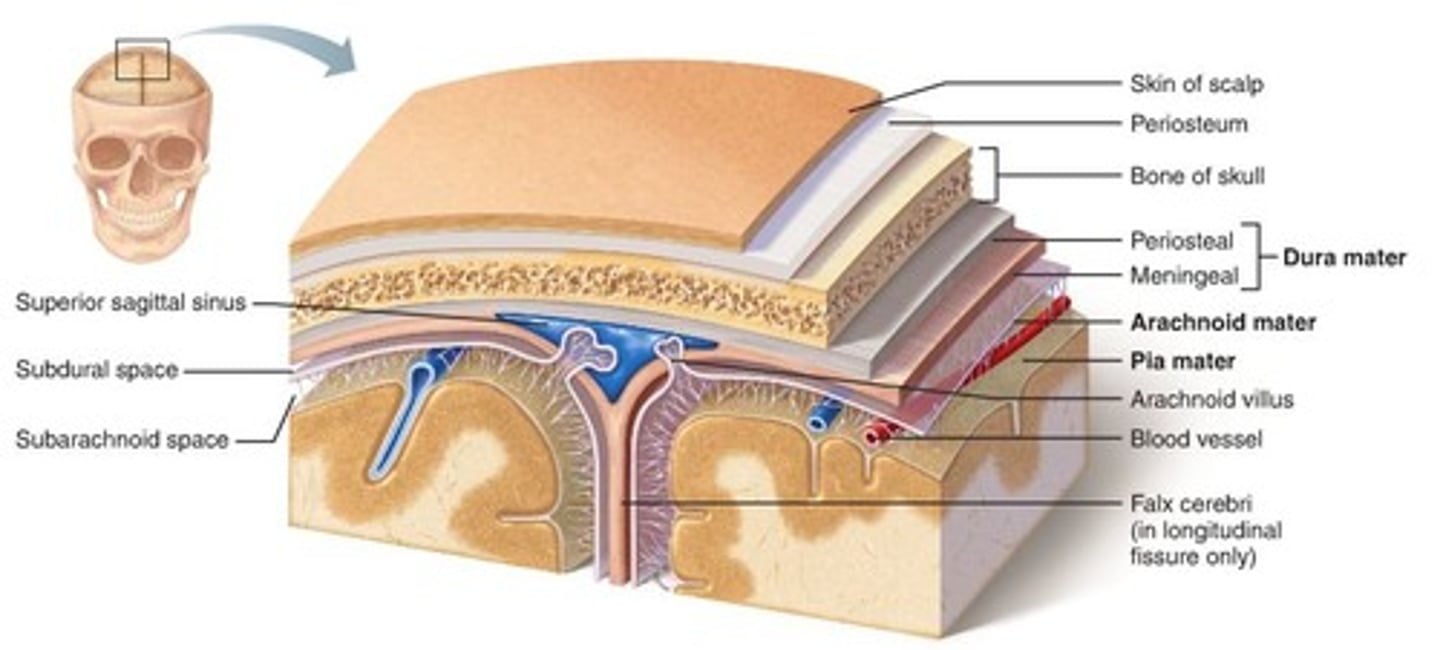

meninges

•Three connective tissue layers

•Separate and support soft tissue of brain

•Enclose and protect blood vessels supplying the brain

•Help contain and circulate cerebrospinal fluid

•From deep to superficial (PAD to protect the brain)

--Pia mater

--Arachnoid mater

--Dura mater

dura mater (brain)

thick, outermost layer of the meninges surrounding and protecting the brain and spinal cord

arachnoid mater (brain)

middle web-like layer of the meninges

pia mater (brain)

thin, delicate inner membrane of the meninges